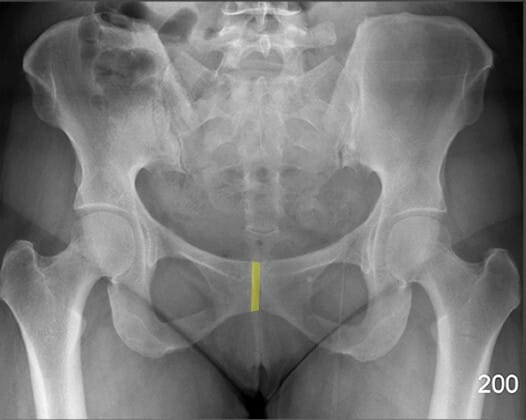

미골 (Coccyx)

| 미골 (Coccyx) |

| ✅ 척추의 가장 하단에 위치한 작은 골절 구조로, 천골 아래에서 정중앙에 위치합니다. |

| 🔴 AP view에서는 짧고 좁은 골 구조로 보이며, 미골 통증(coccydynia)이나 외상 평가 시 주요하게 봐야 합니다. |